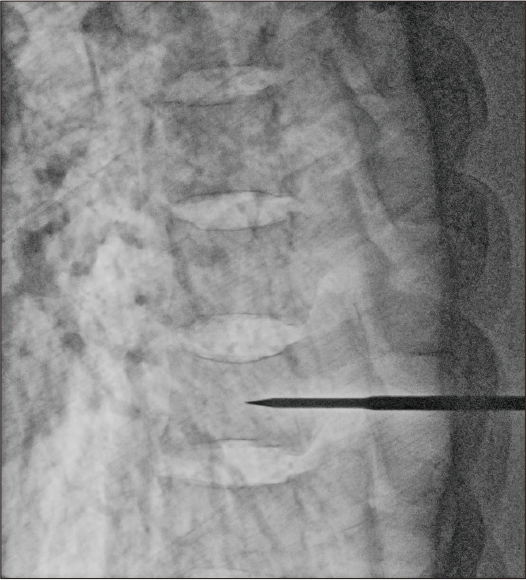

After applying Dynamic processing

Dose: 8.4mA

After applying Dynamic processing + noise reduction